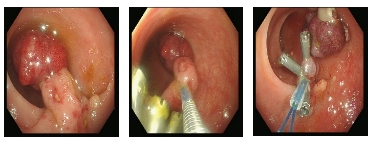

直径>10mm隆起型息肉,根据其蒂部特征选择合适手术。有蒂息肉头部大于20mm或蒂宽大于10mm术后出血风险高,建议注射1:10000肾上腺素和/或机械(尼龙绳或钛夹)止血,然后热圈套器切除。

直肠一枚直径2.5cm长蒂息肉,尼龙绳套扎后圈套器电切,钛夹封闭创面。